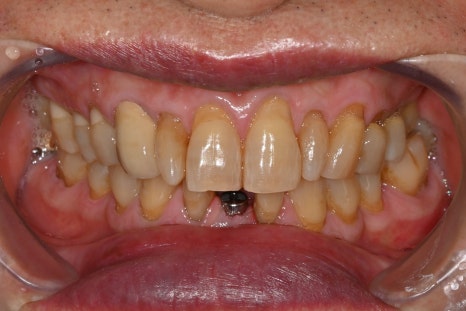

수술 3개월 후 최종보철물까지 장착한 사진

수술 후 3개월 뒤 최종 보철물까지 장착하여

모든 진료가 마무리 되었습니다.